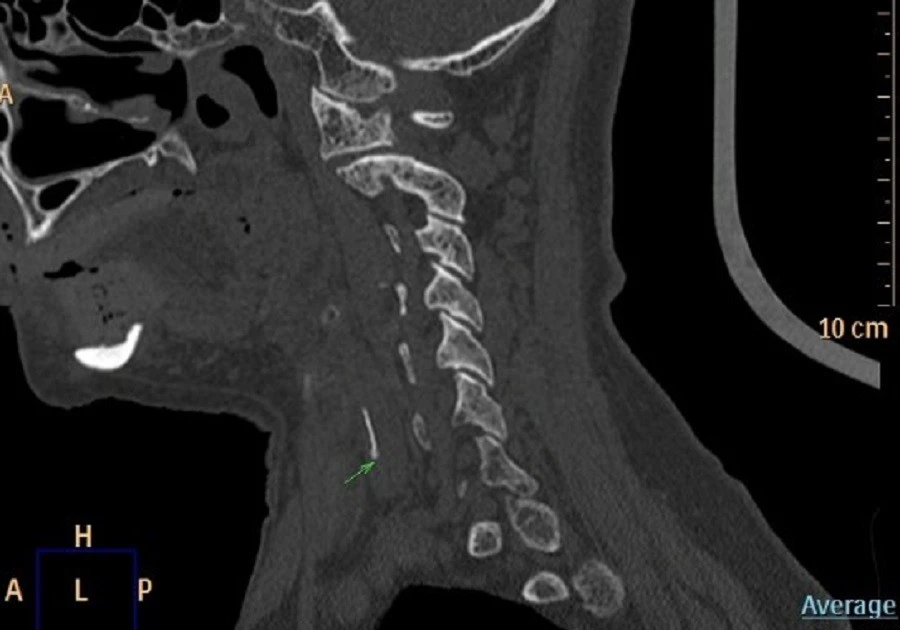

Sau vài ngày, cơn đau không giảm mà còn nặng hơn, khiến bệnh nhân khó ăn uống. Nội soi Tai Mũi Họng cho thấy vùng sụn phễu trái phù nề, còn X‑quang cổ nghi ngờ có dị vật. CT xác định một mảnh xương cá khoảng 1×22 mm đã xuyên qua thực quản và cắm sâu vào thùy trái tuyến giáp, tiềm ẩn nguy cơ nhiễm trùng, áp‑xè cổ và tổn thương các cấu trúc quan trọng.